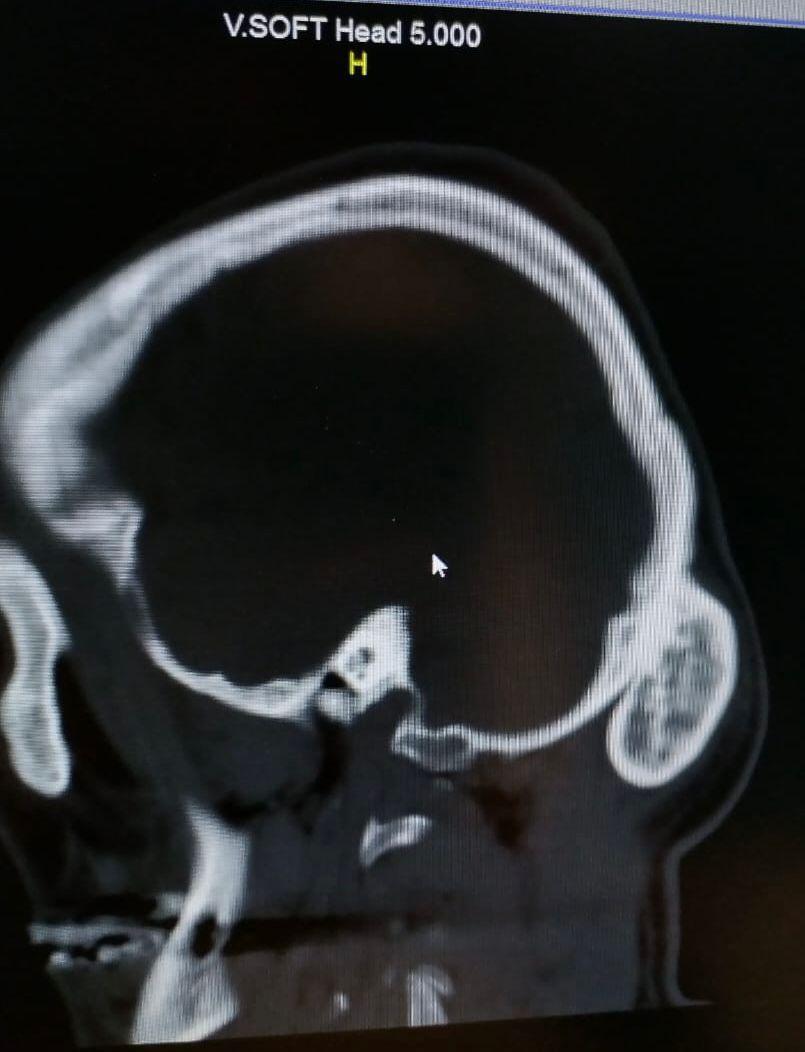

وقال الفريق الطبي ب‘نه فور وصول المريض أجريت له كامل الفحوصات المخبرية والمقطعية على المخ وأشعة ثلاثية الابعاد حيث تبين وجود ورم حميد في القشرة الخارجية من عظام الجمجمة.

وأشار الفريق الطبي بانة تم إدخال المريض الى غرفة العمليات واجراء تدخل جراحي تم خلاله استئصال الورم الذي يزن حجمه (  ٣٠٠ جرام ) وبفضل الله تكللت العملية بالنجاح بعد أن استغرقت أكثر من ساعة ونصف ويتمتع بحالة صحية جيدة حاليا ومازال تحت الملاحظة الطبية.